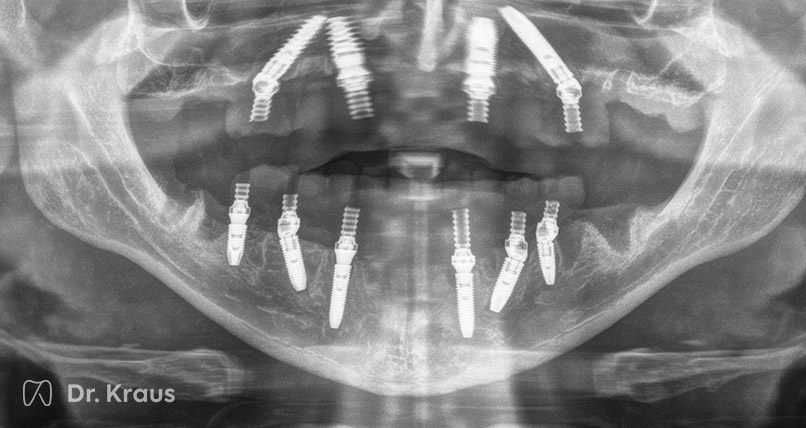

Patientenfall 1

Ausgangssituation

Stark Parodontitis-geschädigtes Gebiss im Oberkiefer mit der Empfehlung alle Zähne zu entfernen durch den vorherigen Zahnarzt als Therapie der Wahl. Starker Knochenrückgang im Oberkiefer.

Behandlungsmaßnahmen

Der Oberkiefer wurde auf Grund des sehr stark zurückgegangenen Knochens mit zwei Zygoma-Implantaten und drei Implantaten versorgt. Im Unterkiefer erfolgte eine klassische All-on-4 Versorgung auf vier Implantaten. Sowohl Ober- als auch Unterkiefer konnten sofort belastet und mit festem Zahnersatz versehen werden (Langzeit-PV).